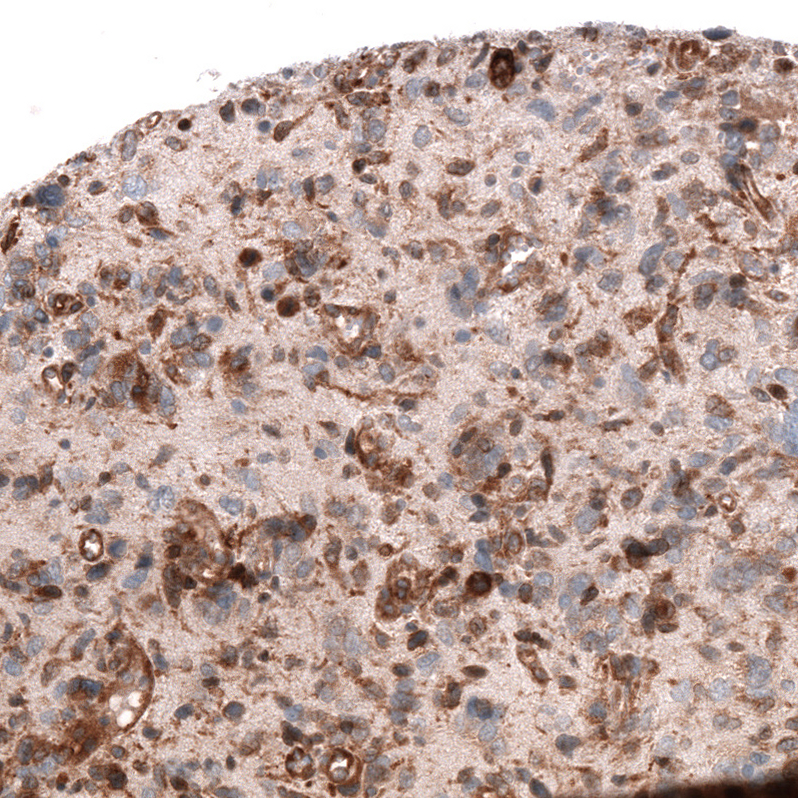

Immunohistochemistry analysis in human prostate and skeletal muscle tissues using AMAb91898 antibody. Corresponding ADAM10 RNA-seq data are presented for the same tissues.